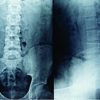

Abstract: Full-length hip-to-ankle radiographs are an important part of planning and execution of any realignment procedure of the lower limb. This technical note describes a simple and inexpensive technique to obtain plain, standing, full-length hip-to-ankle radiograph using regular x-ray plates.

Proper imaging with radiographs plays an important role in preoperative planning and also assessing postoperative radiographic results. One of the major aims of any kind of lower limb corrective surgery such as corrective osteotomy or total knee arthroplasty, is restoration of the mechanical axis of the limb [1]. To achieve this, one needs to be able to assess the existing axis, plan the degree of correction to achieve the desired limb alignment and also to verify whether the post operative alignment obtained was as planned and desired. All these require obtaining proper standing, full-length hip-to-ankle radiographs [2]. However, most centres, especially in developing countries, lack the facilities for obtaining such fulllength radiographs. Typically these full-length radiographs are obtained using a long cassette with an X-ray film of the appropriate length. The X-ray cassette has to be specially made to order, and is expensive because of the three screens that are needed inside. In addition, when a single long cassette is used, one has to use a graduated wedge in front of the x-ray tube, for attenuating the x-ray beam in the lower portion of the cassette to avoid overexposure. We describe here a simple and costeffective technique of obtaining full-length radiographs of the lower limb in a single exposure using 3 standard x-ray cassettes.

We use a simple wooden stand, which can be made by any carpenter, to hold the x-ray cassettes (Fig. 1A). Since the commonly available cassettes are 10 x 12 inches, 12 x 12 inches and 12 x 15 inches in dimension, the transverse length of the stand should be 12 inches. A larger transverse size could be used, provided, three cassettes of the same size are available.

Three regular x-ray cassettes are stacked on each other, length-wise, taking care that none of the joints comes in the area between the cassettes. Two linear markers of a fixed length are placed on either side of the cassette, such that they overly both the upper and the lower cassette equally. We use 8 inch long Kirschner wires for this purpose (Fig. 1B). The patient stands on a low stool so that the plantar surface of the foot is above the edge of the lowermost cassette (Fig. 2). A magnification marker if available is applied in the plane of the bone, and perpendicular

to the x-ray beam.

The x-ray tube is placed 6 feet away, and at the level of the knees (Fig. 2). The exposure factors (KV & maS) used is same as those used for a hip radiograph. This will lead to some overexposure of the lower two cassettes, which can be compensated for by under-developing the x-ray films. In places where automatic processing is used, a triangular aluminium wedge will need to be used to attenuate the beams going to the lower two cassettes. When the films are dried, the three x-rays are kept on a light box of adequate dimensions. Between each of

the three films, one needs to put in a 3 cm strip of (spoilt) film. This simulates the distance between the films when they are in the cassettes (Fig. 3A). The distance between the two intensifying screens is then 3 cms. The correct distance between films can be further judged by using markers of known, equal lengths at all four sites.

Since the markers are practically on the plane, the magnification of the markers is negligible.

Vertical alignment is ensured by keeping the shadows of the markers previously mentioned, in a straight line (Fig. 3B). Since one marker is used on either side, the chances of the films being angled in relation to each other are further decreased. Use of a magnification marker, if available further increases the accuracy of lengths measured from this x-ray. In this position the three films are then joined using transparent tape to create a single, composite, full length x-ray. Relative measurements of limb length discrepancy and angular measurements can now be obtained accurately and reliably. With the use of a magnification marker, even absolute measurements of length can be made very precisely.